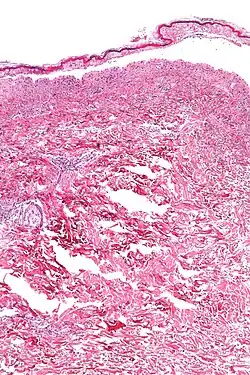

Histologie

Histologisch zeigen sich beim medikamentös induzierten Lyell-Syndrom eine Spaltbildung und Abhebung der gesamten Epidermis, während sich beim staphylogen verursachten Lyell-Syndrom eine Abhebung des Stratum corneum vom Stratum granulosum zeigt.[26]

Bei der medikamentös induzierten Form zeigt sich histologisch eine subepidermale Blase mit einem oberflächlichen Infiltrat aus Lymphozyten und gelegentlich Granulozyten. Die gesamte Epidermis ist abgelöst und nekrotisch mit einem normalen korbgeflechtartigen Stratum corneum. Die Papillen der Dermis sind intakt. Vereinzelt finden sich Extravasate von Erythrozyten.[27]

Die staphylogene Form zeigt histologisch eine nur aus dem Stratum corneum der Haut bestehende Blasendecke, vereinzelt können sich hier Zellen aus dem Stratum granulosum finden. Es finden sich spärliche entzündliche Infiltrate, der Blaseninhalt ist steril.[27]